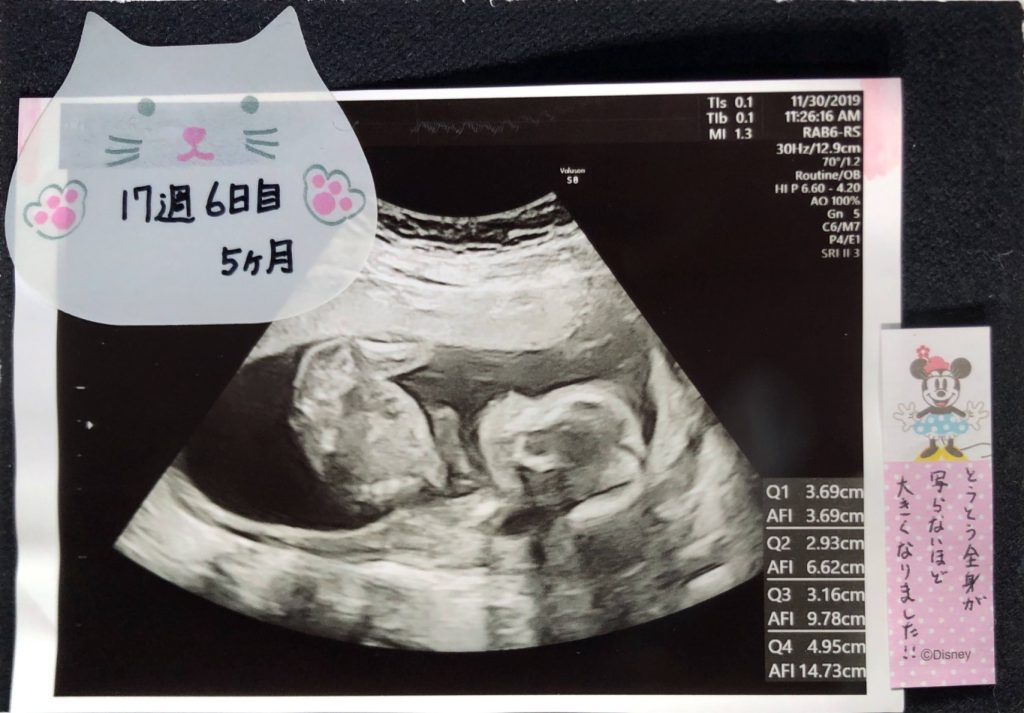

前回はエコー写真をデジタルにされていた方もいましたよ!